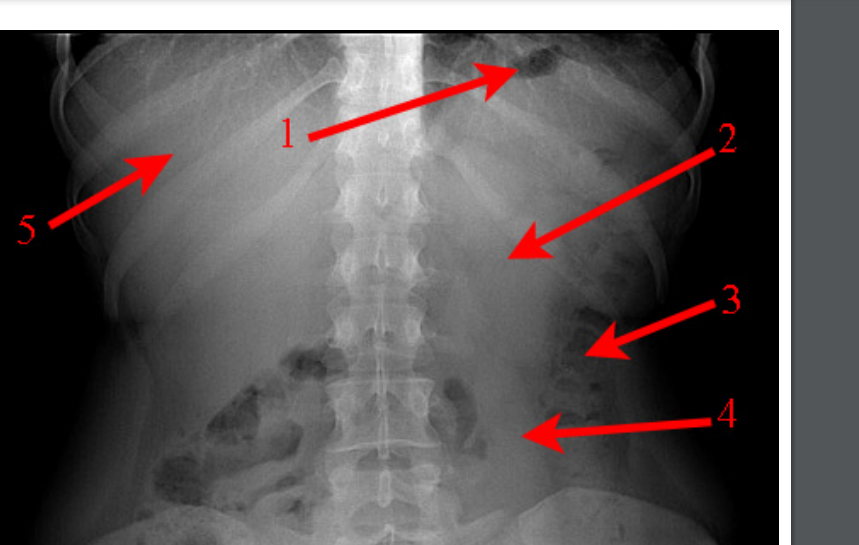

Identifie les structures anatomiques

A

1. bulle d’air gastrique

2. rein gauche

3. colon descendant

4. rein gauche

5. foie